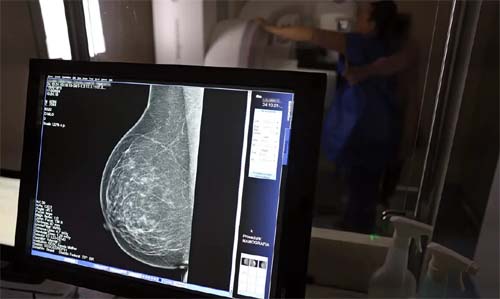

Direitos Previdenciários para Mulheres com Câncer de Mama no Brasil

Como garantir benefícios durante o tratamento e as estimativas do Inca para 2025

Durante a campanha Outubro Rosa, o Instituto Nacional de Câncer (Inca) projetou que neste ano ocorrerão 73.610 novos diagnósticos da doença no país, a principal causa de mortalidade entre mulheres brasileiras. Identificadas com câncer de mama, muitas dessas pacientes podem solicitar auxílio-doença ou o Benefício de Prestação Continuada (BPC/LOAS).